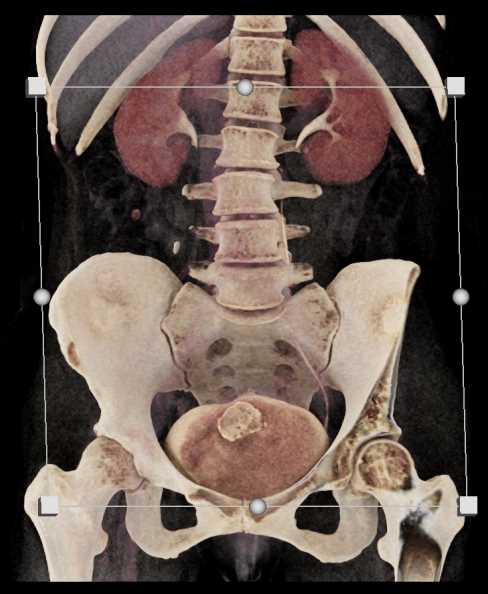

Urachal Carcinoma of the Bladder